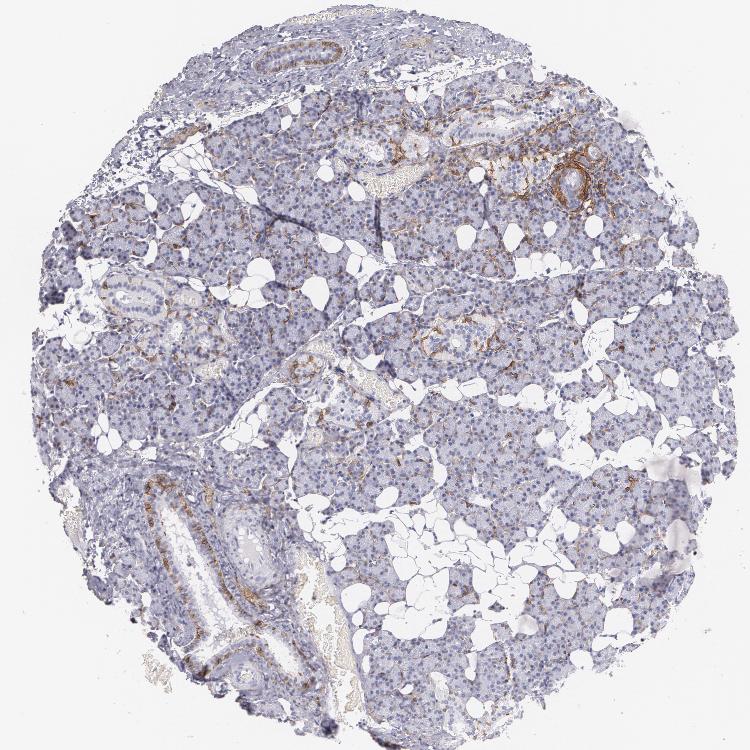

SALIVARY GLAND - Antibody stainingi

Antibody staining in the annotated cell types in the current human tissue is reported as not detected, low, medium, or high, based on conventional immunohistochemistry profiling in selected tissues. This score is based on the combination of the staining intensity and fraction of stained cells.

Each image is clickable and will lead to virtual microscopy that enables deeper exploration of all samples and also displays staining intensity scores, fraction scores and subcellular localization as well as patient and tissue information for each sample.

Antibody HPA004765Antibody CAB000143Antibody CAB001995

Glandular cells LowNot detectedLow